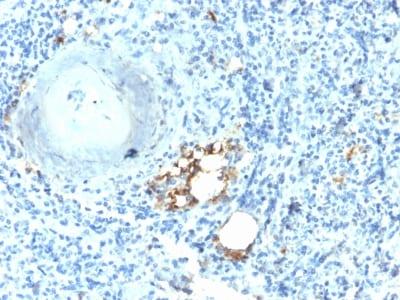

This antibody recognizes a protein of 35 kDa, which is identified as tartrate-resistant acid phosphatase (TRAcP). It exists as two isoforms (5a and 5b). This MAb reacts with both the isoforms. Serum TRAcP 5a is secreted by macrophages and dendritic cells and increased in many patients of rheumatoid arthritis. Serum TRAcP 5b is produced from osteoclasts and elevated during bone resorption. TRAcP is an iron containing glycoprotein, which catalyzes the conversion of orthophosphoric monoester to alcohol and orthophosphate. It is the most basic of the acid phosphatases and is the only form not inhibited by L( )-tartrate. TRAcP is synthesized as a latent proenzyme and is activated by proteolytic cleavage and reduction. Normally, TRAcP is highly expressed by osteoclasts, activated macrophages, neurons and endometrium during pregnancy. Expression of TRAcP is increased in certain pathological conditions such as Leukemic Reticuloendotheliosis (Hairy Cell Leukemia), Gaucher s Disease, HIV-induced Encephalopathy, Osteoclastoma and in osteoporosis and metabolic bone diseases. Anti-TRAcP antibody labels the cells of Hairy Cell Leukemia (HCL) with a high degree of sensitivity and specificity. Other cells stained with this antibody are tissue macrophages and osteoclasts.Primary antibodies are available purified, or with a selection of fluorescent CF® Dyes and other labels. CF® Dyes offer exceptional brightness and photostability. Note: Conjugates of blue fluorescent dyes like CF®405S and CF®405M are not recommended for detecting low abundance targets, because blue dyes have lower fluorescence and can give higher non-specific background than other dye colors.

HepG2, 293T, K562 or RPMI-8226 Cells. Spleen from Hairy Cell Leukemia (HCL) patient.